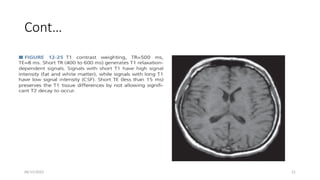

T1 Weighting

• A “T1W” SE sequence is designed to produce contrast chiefly based on the T1

characteristics of tissues,

• with de-emphasis of T2 and proton density contributions to the signal.

• Achieved by using a relatively short TR to maximize the d/c in longitudinal

magnetization recovery during the return to equilibrium,&

• a short TE to minimize T2 decay during signal acquisition

• T1W SE contrast requires a short TR and a short TE (spin-lattice relaxation time)

• Fat is the most intense signal, followed by white matter, gray matter, and CSF.